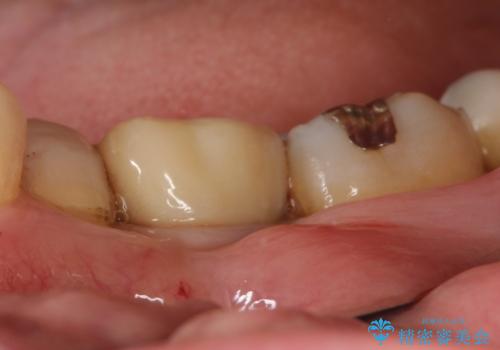

メタルインレーの下は。クラックラインを認めた歯。

- 定期検診にて、奥歯にクラックラインを認めました。

放置すると、抜歯になる可能性も高いため早めの治療を提案し、クラウンにて修復治療を行なっております。

術前説明にてクラックラインを認めることや治療の選択肢及び予後について理解していただいた上で、保存を希望されております。歯髄症状が出なかったため抜髄はせずに治療を完了しております。